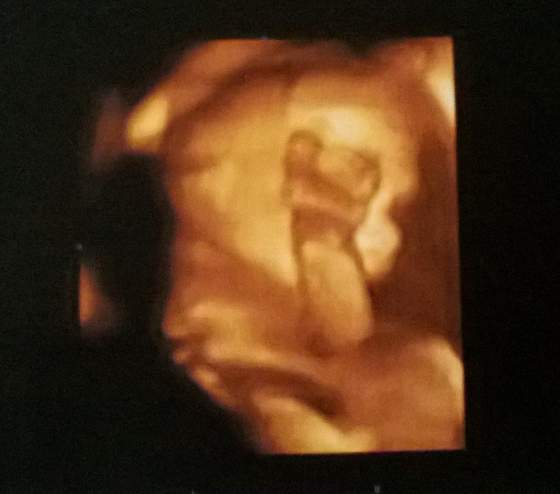

21+3 - taki obrażony :-p